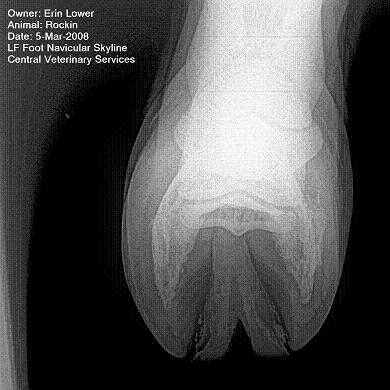

So, Rockin's x-rays were sent to a radiologist and he confirmed "normal" changes in the navicular bones for a horse her age, but slightly more significant ones in the right (sore) foot.

She also has sidebone in both fronts, but apparently that isn't causing any discomfort.

Finally, she has a "small chronic exostosis on the lateral aspect of the proximal phalanx" which, according to the radiologist, shouldn't be causing discomfort but I have read that these can be mild-to-moderately painful... I wouldn't mind another opinion on that.

I will attach as many images as possible from her x-rays (there are many different views). I don't have any pics of the feet as someone deleted them from my camera before I could download them. I'll try to take pics next time she is trimmed. Please, anyone with knowledge of hooves, give any opinions that you might have (especially Dr. O!)

I cannot rule out lesions based on these images but I will take your radiologist's word that he does not see significant lesions. The exostosis on the RF would be above the level of a well conducted PDN which I believed blocked the lameness before?

DrO